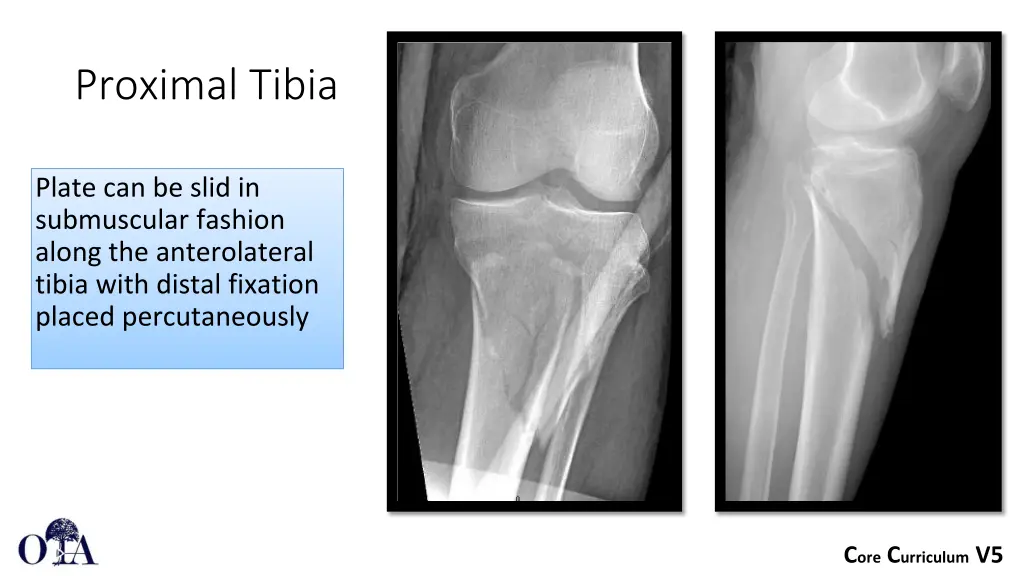

Proximal Tibia Plate can be slid in submuscular fashion along the anterolateral tibia with distal fixation placed percutaneously Core Curriculum V5